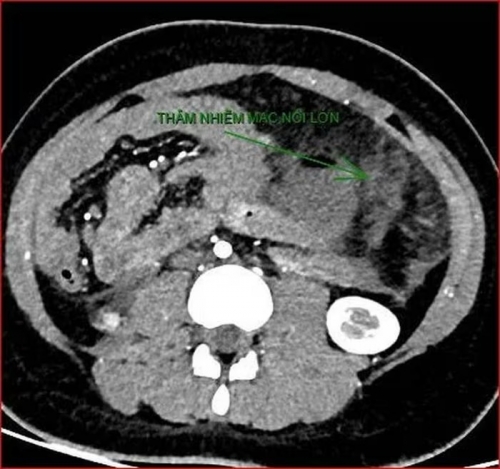

Khoảng 21h40, kết quả chụp CT cho thấy bệnh nhân rơi vào tình trạng cực kỳ nặng và hiếm gặp, bao gồm: Xoắn dạ dày, nhồi máu thận trái, nhồi máu lách, viêm đầu tụy, viêm hỗng tràng, kèm dịch ổ bụng và tràn dịch màng phổi, trên nền bệnh nhân mắc hội chứng Down và tim bẩm sinh.

Kết quả chụp CT cho thấy bệnh nhân rơi vào tình trạng cực kỳ nặng và hiếm gặp. |